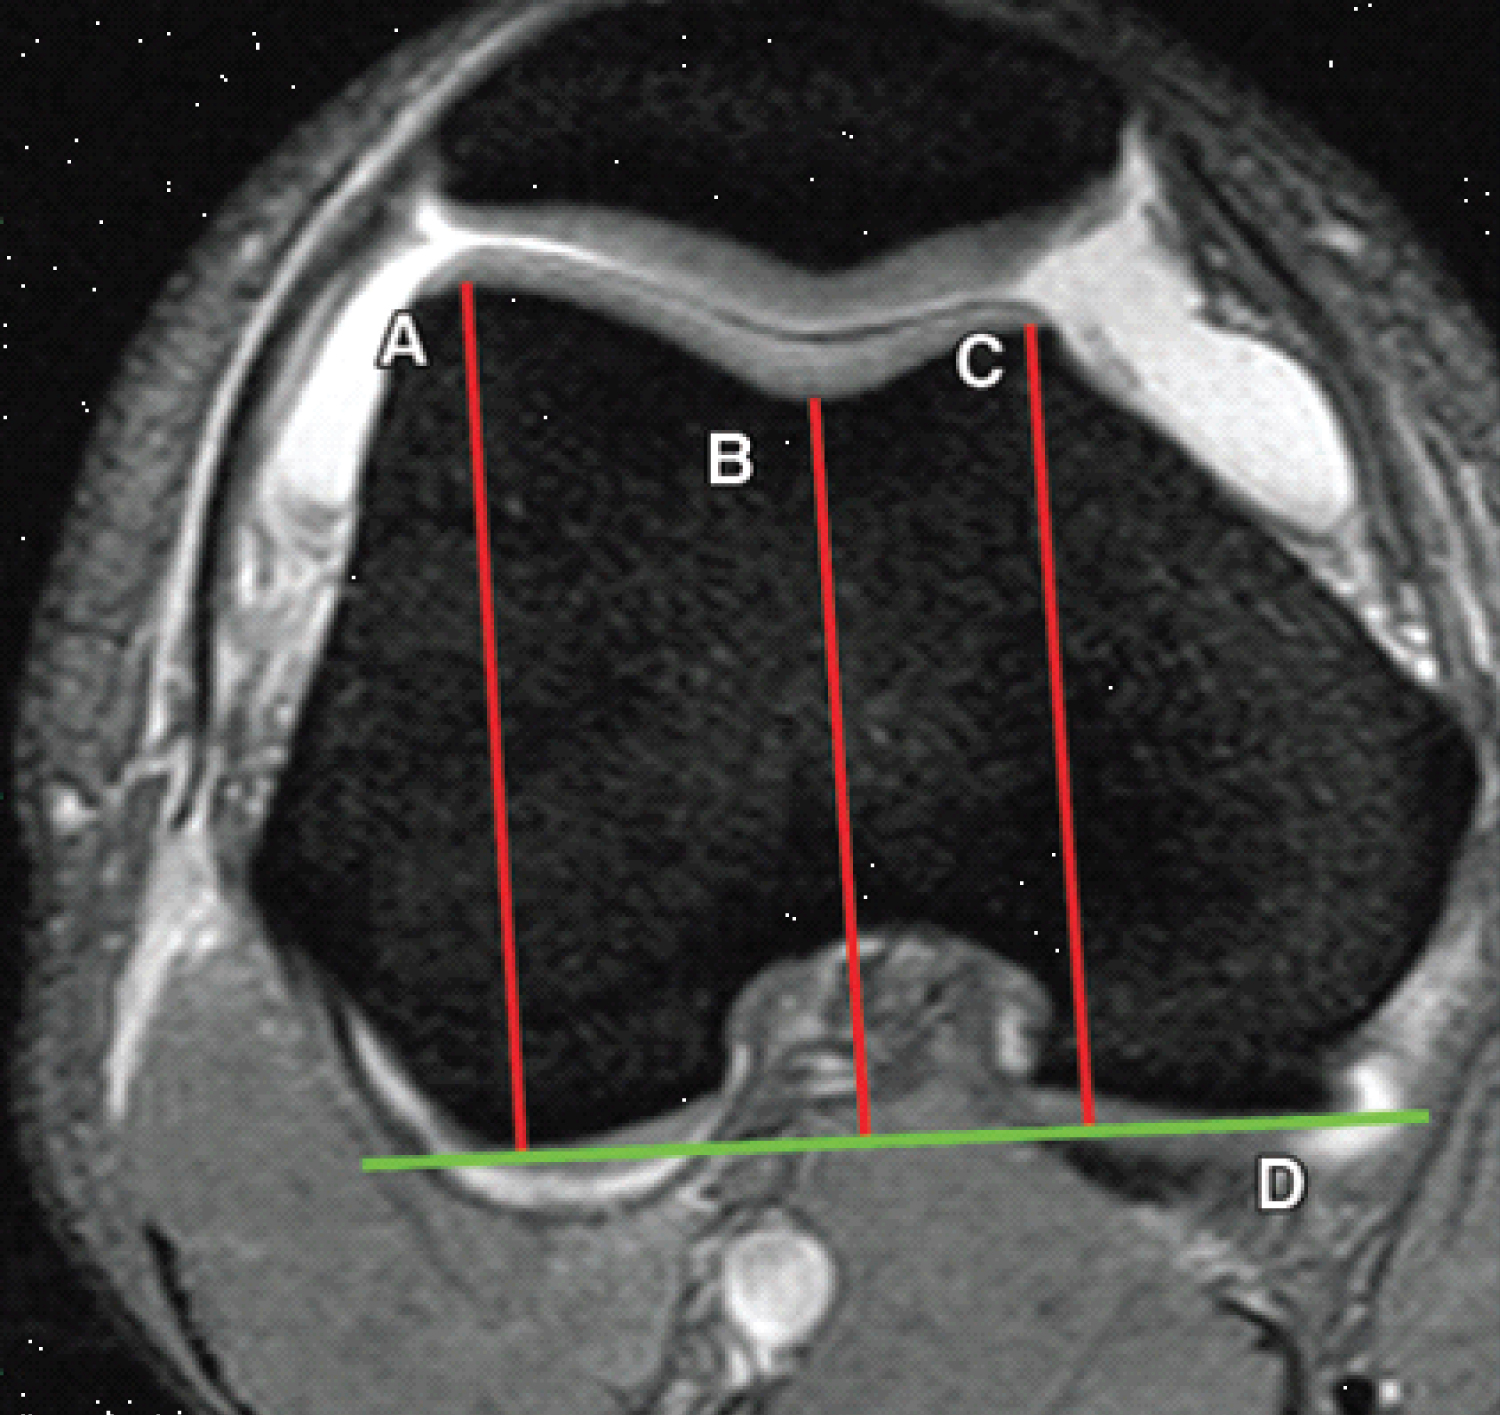

c) Depth of the trochlear groove, MRI slices at about 3 cm above the tibio-femoral joint space were used for the assessment of the trochlear depth by measuring the maximal antero-posterior distance of the medial femoral condyle (distance a) and lateral femoral condyle (distance b), and the minimal antero-posterior distance between the deepest point of the trochlear groove and the line paralleling the posterior outlines of the femoral condyles (distance c) (Figure 5). Trochlear depth was calculated by the formula ([a + b]/2)-c). Trochlear dysplasia is assumed if the trochlear depth is 3 mm or less [7].

Figure 5: Trochlear depth assessed on axial fat-saturated T2-weighted MR images. A line drawn parallel to the posterior aspect of the femoral condyles serves as a reference line (line D). The lines drawn perpendicular to the reference line indicates the largest anteroposterior diameters of the lateral (line A) and medial (line C) trochlear facets and the deepest point of the sulcus (line B). Trochlear depth is calculated as follows: (A + C/2) - B). A trochlear depth of 3 mm or less is assumed to indicate dysplasia. View Figure 5